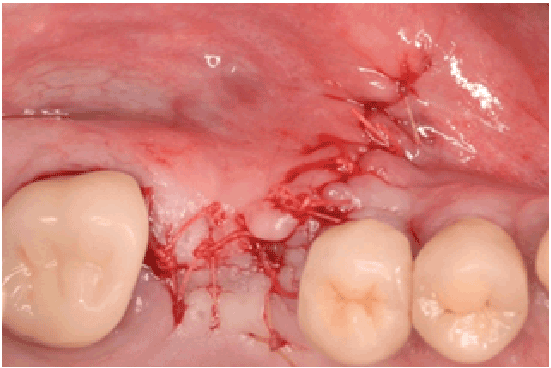

图2:再入时前骨窗上方的部分厚度皮瓣

图2 b:新厚窦膜剥离

图2 c:新厚窦膜的升高

图2 d:植骨及植入物

所有穿孔(>10 mm)在手术期间使用位于骨窗延伸后窦侧壁和穿孔的Scheiderian膜之间的可吸收胶原膜(collapape®,Integra LifeSciences Corp., Plainsboro, NJ)修复(图1f)。采用可吸收缝线(4-0 Chromic Gut, Johnson & Johnson, New Brunswick, NJ)完成皮瓣一期缝合(图1g和1h)。然后在3到6周的愈合时间后进行鼻窦再入路手术,以实现鼻窦增强手术。抬高全层皮瓣,暴露初始骨窗,需要剥离软组织(图2a),以便能够抬高愈合的施耐德膜(图2b)。由于在之前的手术中没有使用移植物材料来填充鼻窦,因此鼻窦被移植了无机牛骨基质(ABBM) (Bio-Oss®(图2c和2d)和可吸收膜(Bio-Guide)®,Geistlichpharma,Princeton,NJ)被放在窗户上方。